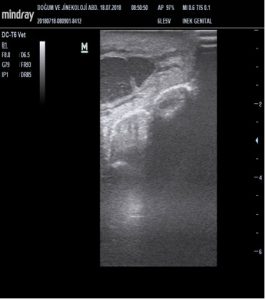

Şekil 3. Veteriner Amaçlı Argon Plazma Koagulasyon Cihazı’nın meme başına uygulanmadan önce tıkalı meme başının ultrasonografik görüntüsü |

Şekil 3. Veteriner Amaçlı Argon Plazma Koagulasyon Cihazı’nın meme başına uygulanmadan önce tıkalı meme başının ultrasonografik görüntüsü